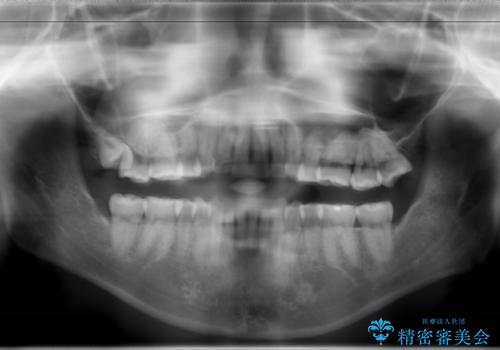

骨格的要因を背景にもつ不正咬合のため、歯列矯正単独での改善は困難と判断しましたが、患者さんとの相談の結果、歯列矯正単独で可能なところまで一緒に頑張りましょうということで、治療をすすめました。

シビアな叢生や開咬も改善することができ、想像以上の改善に時間をかけた甲斐があったと満足していただけました。